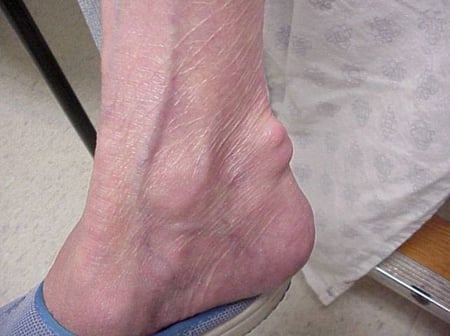

Gout flares can occur in joints that look normal, or in joints that have easily visible deposits of uric acid. These deposits are called tophi (See Figures: 7a and 7b: Tophi on Foot and Over Achilles' Tendon, Figure 8: Tophus on Elbow, Figure 9: Tophi on Hands, and Figure 10: Large Tophus of Finger) and can be in numerous locations, but especially on the feet and elbows. In Figure 9, the little finger of the right hand is bandaged since fluid was just removed from it, which demonstrated innumerable uric acid crystals.

Photo showing tophus over the Achille's tendon

Figure 7b: Tophus Over Achilles' Tendon